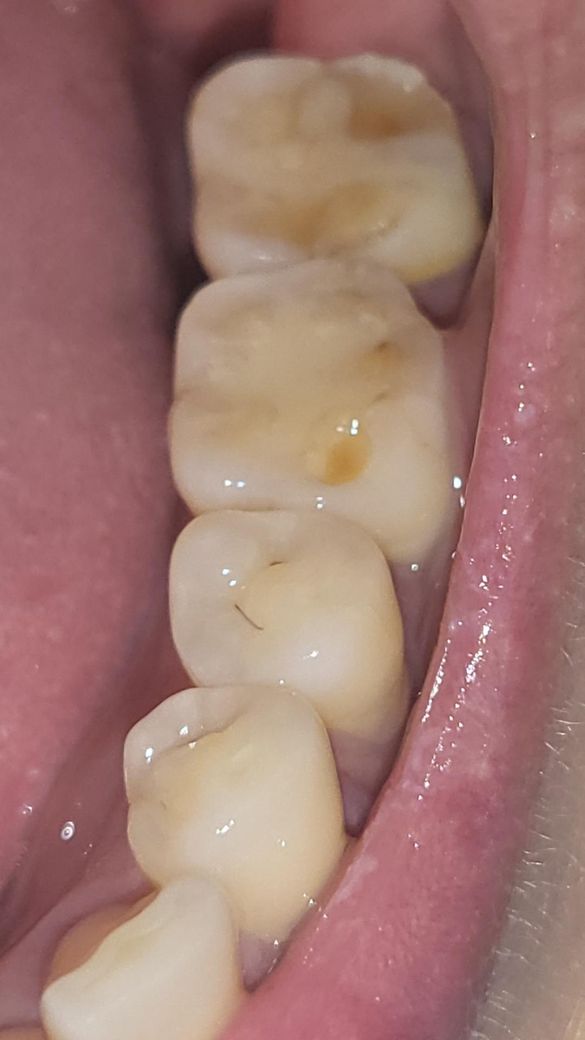

그 이후 임신과 출산,이갈이(마우스피스 미착용) 기간을 거치면서 해당 어금니가 현재는 깨져 있고, 씹는 면 중앙에 노란색으로 상아질이 노출된 상태입니다. 통증이나 욱신거림은 없으나 색 변화와 미세한 파절이 육안으로 보입니다.

상아질이 노출되어 있으나 치아 특정 부위가 깨져서 그런 것은 아니고 전반적으로 마모가 있어서 그렇습니다. 이런 경우 신경치료가 필요하지는 않을 확률이 높으나 마모의 원인은 찾아 해결하는 것이 좋습니다.

크라운이고, 레진이고 마모의 원인이 이갈이나 이악물기면 치아는 또 금방 망가집니다.